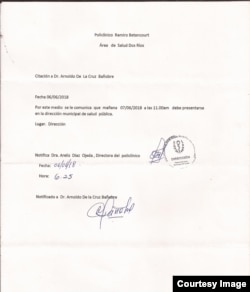

El tribunal municipal de Palma Soriano, en Santiago de Cuba, citó a juicio mañana miércoles al médico opositor Arnoldo de la Cruz por el supuesto delito de "propagación de epidemias", según explicó al Programa Cuba Al Día.

Sin embargo es probable que se postergue la vista oral, debido a que la jueza ha devuelto el expediente a la policía, de acuerdo a la información ofrecida por De la Cruz este martes al periodista Adriel Reyes, de Radio Martí.

Por último, cinco días después apareció un instructor policial para tomar sus declaraciones "porque la Dirección Municipal de Salud Pública me había acusado de propagación de epidemias", concluyó.

Mañana miércoles será el juicio en contra del doctor Arnoldo de la Cruz. Oficiales le dijeron que en Palma Soriano hay al menos otras tres personas acusadas del mismo supuesto delito.